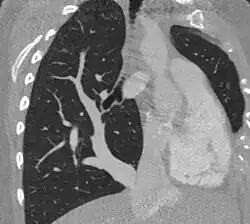

| Scimitar syndrome chest CT | |

Scimitar syndrome, or congenital pulmonary venolobar syndrome, is a rare congenital heart defect characterized by anomalous venous return from the right lung (to the systemic venous drainage, rather than directly to the left atrium).[1] This anomalous pulmonary venous return can be either partial (PAPVR) or total (TAPVR). The syndrome associated with PAPVR is more commonly known as Scimitar syndrome after the curvilinear pattern created on a chest radiograph by the pulmonary veins that drain to the inferior vena cava.[2] This radiographic density often has the shape of a scimitar, a type of curved sword.[2] The syndrome was first described by Catherine Neill in 1960.[3]

The anomalous venous return forms a curved shadow on chest x-ray such that it resembles a scimitar. This is called the Scimitar Sign. Associated abnormalities include right lung hypoplasia with associated dextroposition of the heart, pulmonary artery hypoplasia and pulmonary sequestration. Incidence is around 1 per 100,000 births.[4]